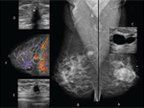

FIGURE 1

Examples of mammographic images from 1940 to 2006

Mammography is a low-dose x-ray examination of the breasts performed with dedicated imaging equipment to detect abnormalities that may be breast cancer. The image receptor in modern mammography equipment is either screen-film or digital. Full-field digital mammography (FFDM) has largely replaced screen-film units over the past decade, and according to the US Food and Drug Administration (FDA), 88% of all accredited mammography units in the US are FFDM units.[10] Dedicated mammography equipment is specifically designed to produce high-quality images of the breast at a minimum x-ray dose (approximately 3 to 4 mGy per view).[11] In the US, image quality and interpretive skills have also been improved through early efforts by the American College of Radiology’s Mammography Accreditation Program (ACRMAP), and subsequently as a result of the passage of the Mammography Quality Standards Act (MQSA) of 1992, which requires a facility to meet a broad range of technical and personnel standards in order to be certified by the US Food & Drug Administration (FDA).[12] The incremental improvement in image quality is evident in examples of mammograms derived from different mammography imaging technologies from the 1940s to today (Figure 1).